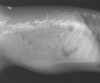

写真は最近、たばる動物病院で手術した症例の手術前の脊髄造影と手術中のものである。手術が必要な箇所は、椎間板が石灰化している部位(第12胸椎-第1腰椎間、第1腰椎-第2腰椎間の2箇所)ではなく、真の脊髄圧迫部位は第2第-3腰椎間(矢印)であることが判る。